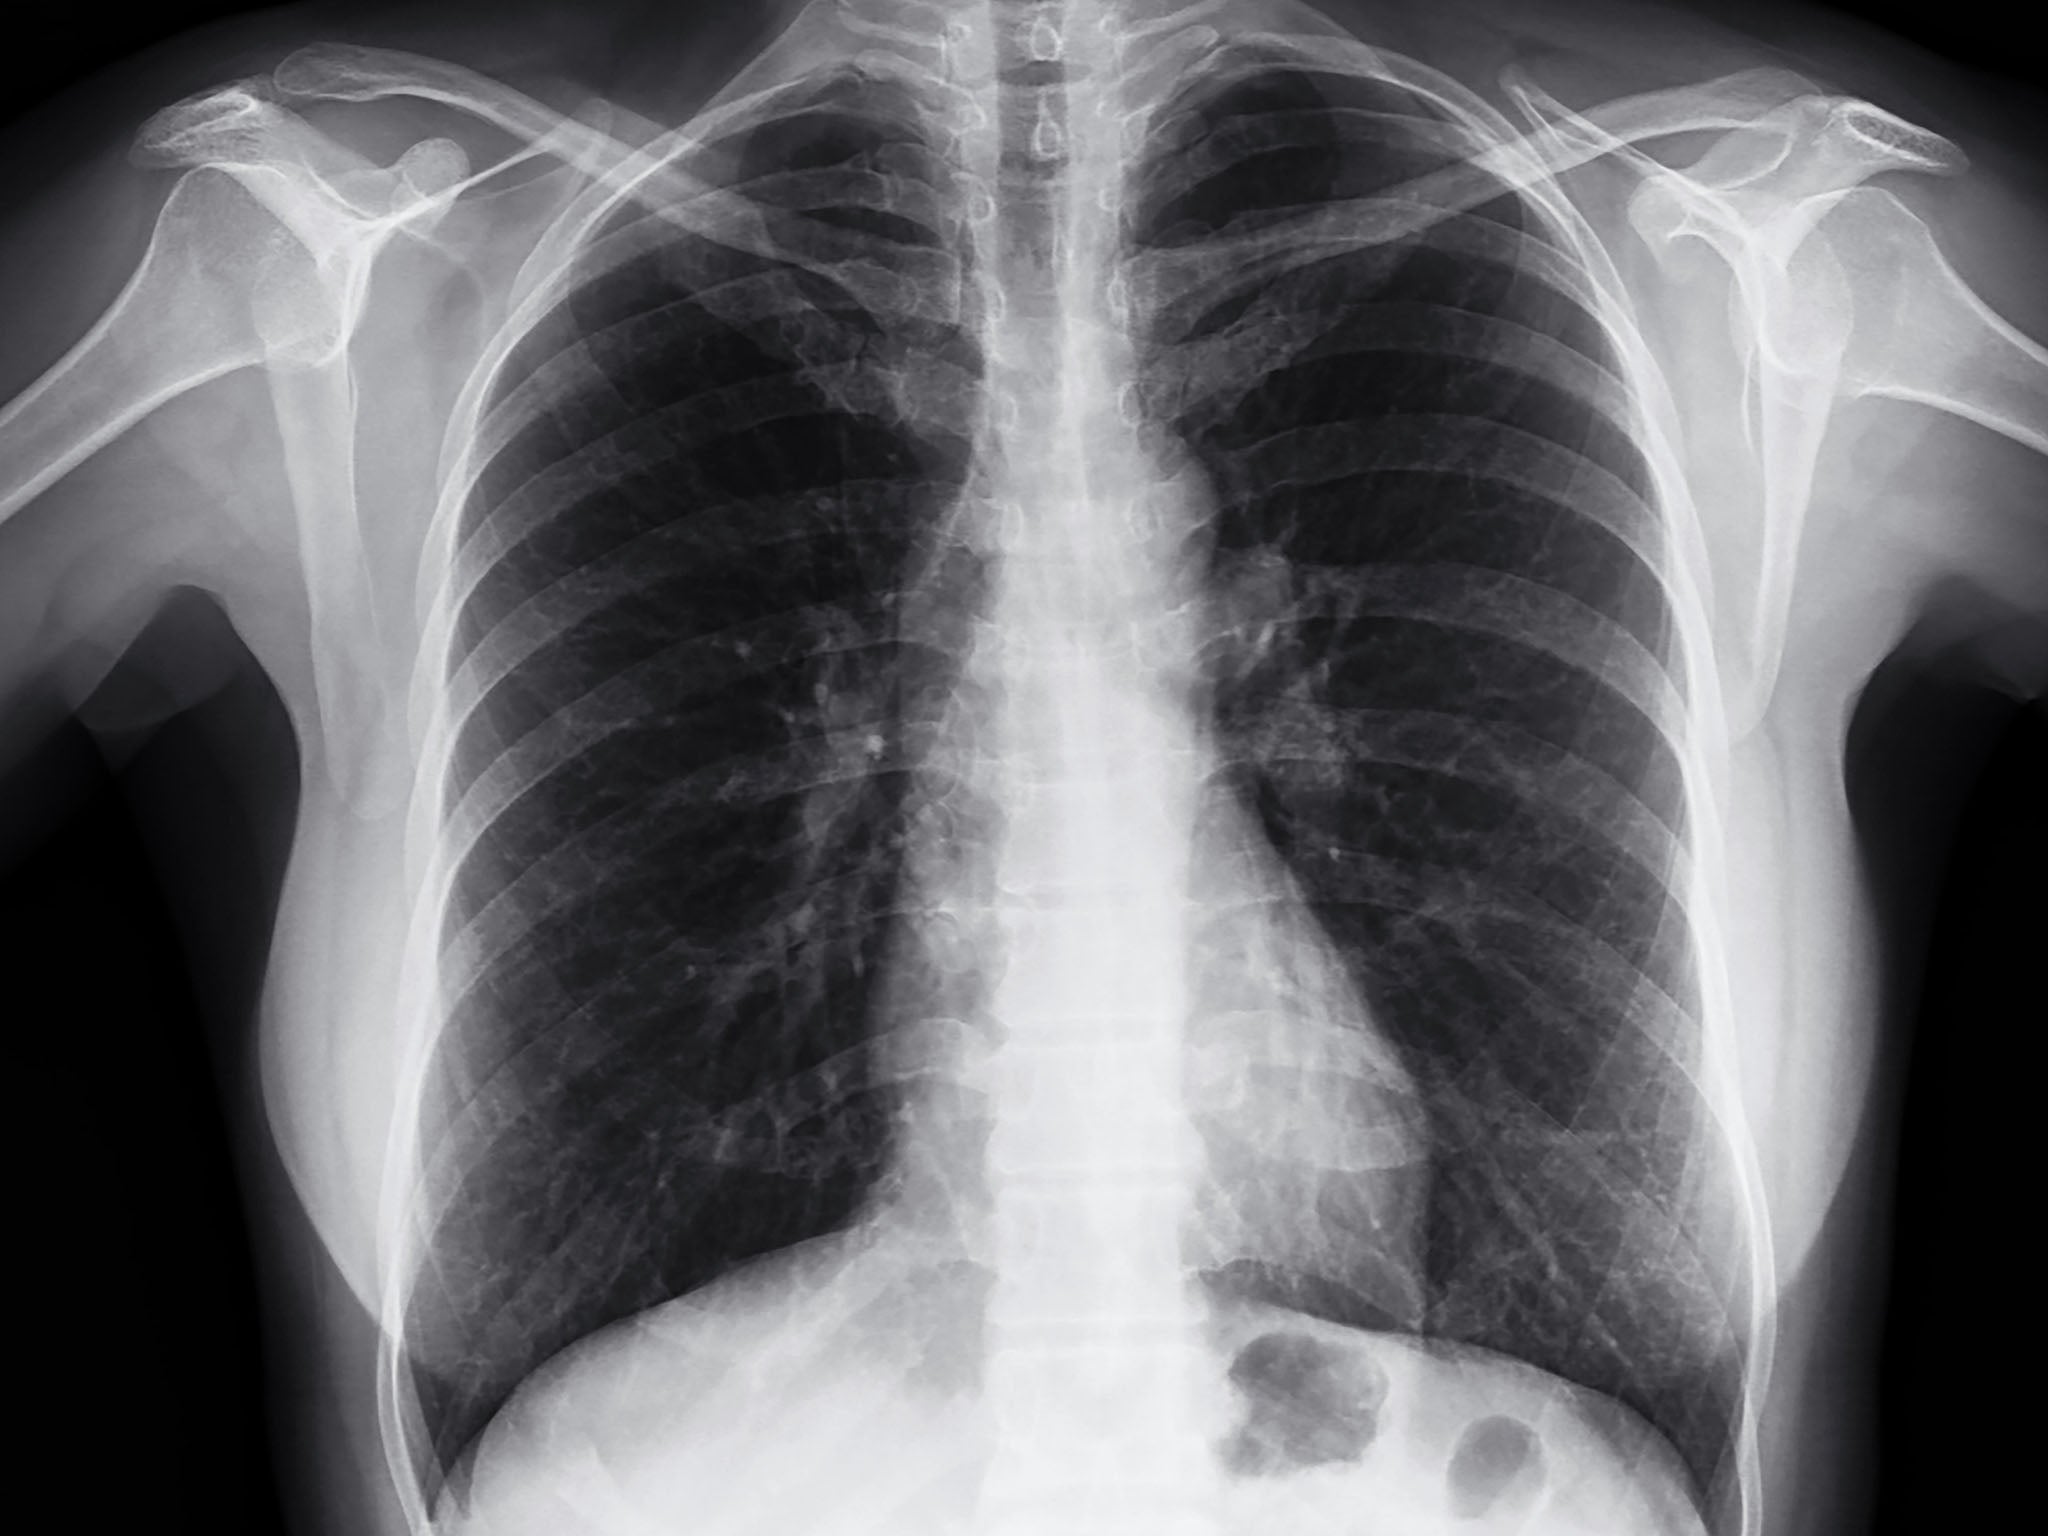

When examining a chest X-ray, it’s crucial to assess the lungs by comparing the upper, middle, and lower zones on both sides. Asymmetry in lung density may appear as either abnormal whiteness (increased density) or abnormal blackness (decreased density). Once asymmetry is identified, the next step is determining which side is abnormal. If an area differs from the surrounding lung tissue on the same side, it is likely the abnormal region.

Lung zones

Assess the lungs by comparing the upper, middle and lower lung zones on the left and right. Asymmetry of lung density is represented as either abnormal whiteness (increased density), or abnormal blackness (decreased density). Once you have spotted asymmetry, the next step is to decide which side is abnormal. If there is an area that is different from the surrounding ipsilateral lung, then this is likely to be the abnormal area.

Consolidation

If the alveoli and small airways fill with dense material, the lung is said to be consolidated.

It is important to be aware that consolidation does not always mean there is infection, and the small airways may fill with material other than pus (as in pneumonia), such as fluid (pulmonary oedema), blood (pulmonary haemorrhage), or cells (cancer). They all look similar and clinical information will often help you decide the diagnosis.

Air bronchogram

If an area of lung is consolidated it becomes dense and white. If the larger airways are spared, they are of relatively low density (blacker). This phenomenon is known as air bronchogram and it is a characteristic sign of consolidation.